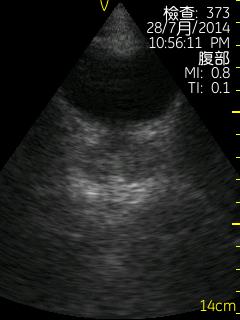

Vscan临床图片 腹部